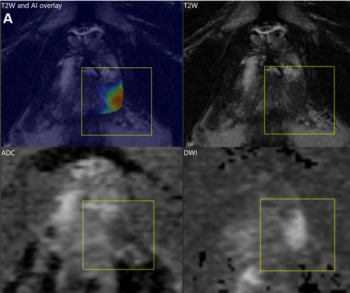

Examining the use of the Response Evaluation Criteria in Prostate-specific Membrane Antigen (PSMA) PET/CT (RECIP 1.0) model for assessing the treatment of metastatic castration-resistant prostate cancer, researchers found robust agreement between quantitative application of RECIP via tumor segmentation software and qualitative application of the model through reads by nuclear medicine physicians.